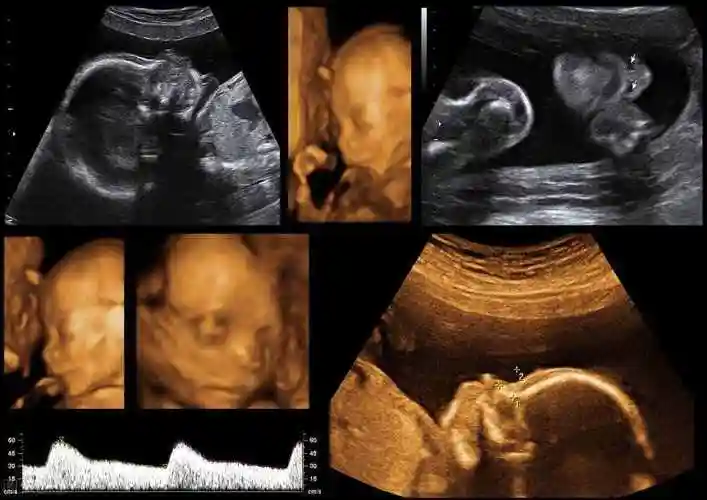

相关图片

四维拍出来,当时一看好丑啊,这鼻子也太大了,我的显性基因也太强了

双胎小棉袄四维 我们凑成了一个好字

四维出来的时候发照片给我姐,她说怎么看着这么丑啊,真的很丑吗?

为什么胎儿四维照"丑相"?b超医生告诉你真相,原因是这三点